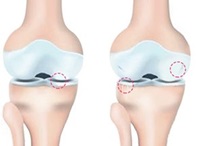

콘드로이친이 부족할 경우 연골은 보수성과 탄력을 잃는다고 합니다. 연골이 계속에서 닳게 되는 경우에는 뼈끼리 마찰이 생겨 부딪히게 되며 관절통이 진행되어 관절염 또한 쉽게 생길 수 있는데요. 콘드로이친 효능 중 가장 잘 알려진 관절통증을 완화시키는 역할을 통하여 얇아서 닳기 쉬운 연골의 마모를 방지해주는 일을하며 관절염의 통증을 개선하는데 도움이 됩니다.

콘드로이친이 연골을 재생시키고 보수성을 높이면서 무릎에 받을 수 있는 충격과 마찰을 흡수시키는 역할을 해 연골을 보호하는일을 하는데요. 실제 연구에서도 4개월간 꾸준히 콘드로이친 1200mg 정도를 섭취한 실험군에게서 관절과 연골의 통증이 43%이상 감소했다는 결과가 있습니다.